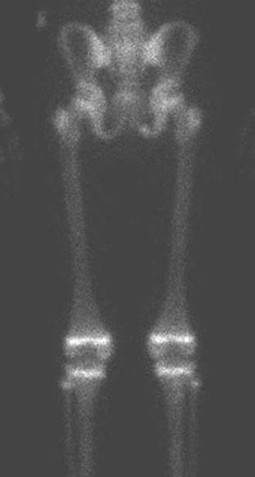

Wat is een botscan?

Een botscan, ook wel skeletscintigrafie genoemd, is een scan van het skelet die wordt gemaakt nadat er een licht radioactieve stof is ingespoten via een infuus. Na het inspuiten van de radioactieve stof moet je een tijdje wachten zodat deze kan worden opgenomen in de botten en gewrichten. Op plekken waar meer activiteit is, verzamelt zich meer radioactieve stof. Met behulp van een gammacamera kan dit in beeld worden gebracht.

Botscan van het bekken, bovenbenen en knieën van een kind van 10 jaar. Op plekken waar het skelet hard groeit, zoals de groeischijven rond de knieën, is veel activiteit zichtbaar. Er zijn geen afwijkingen.

Tijdens het maken van de scan lig je op je rug. De gammacamera wordt vlak boven je gepositioneerd om de radioactiviteit goed te kunnen opvangen.

Met behulp van een botscan kan worden gekeken of er sprake is van een infectie rond een heupprothese.